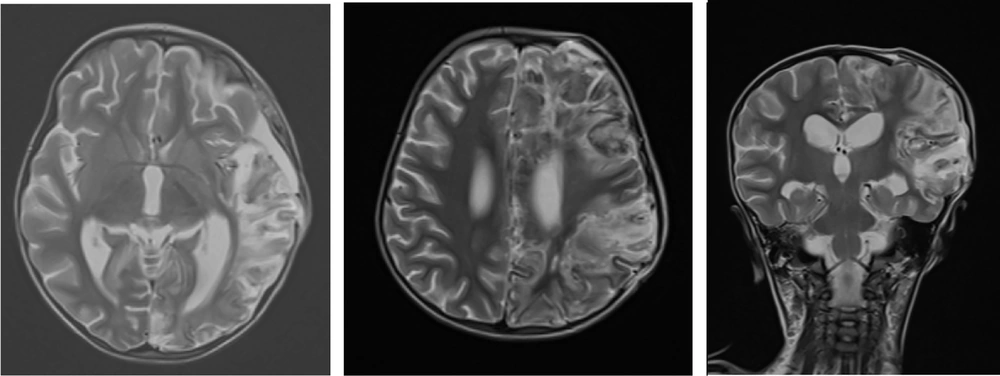

Three days after successful extubation, the patient demonstrated abnormalities in limb tone and force, as well as anisocoria. Brain MRI showed severe generalized edema, ischemia, and herniation (Figure 2). Antiepileptic drugs were started due to brain damage. Following a severe increase in intracerebral pressure, a craniotomy was performed, and supportive treatment continued. A brain biopsy showed inflammation and bleeding. MRA (Magnetic Resonance Angiography) showed a filling defect in the right vertebral artery. Post-craniotomy MRI reported mild herniation through the craniotomy site. An abnormal T2/FLAIR high signal was noted in the left cerebral hemisphere, left basal ganglia, and left thalamus as a sequel of infarction. Hemorrhagic changes in the left frontal lobe were seen, with multiple areas of gyral T1-high signal mostly suggestive of cortical laminar necrosis (Figure 3). There were no changes in favor of HSV in the MRI. Post-craniotomy CT scan showed parenchymal edema and hemorrhagic changes in the left frontal lobe, with abnormal hyper-dense foci noted in the genu and splenium of the corpus callosum and left caudate nucleus (Figure 4). The patient was diagnosed with cerebral stroke. CSF PCR for HSV from the brain biopsy, serum HLA B51, IgA, IgG, IgM, IgE, ANA, lupus anticoagulant, TG, cholesterol, HDL, LDL, pANCA, cANCA, anti-coagulant IgG and IgM, anti-cardiolipin IgG and IgM, protein C, protein S, anti-thrombin 3, F-ANA, anti-B2 glycoprotein, anti-DNase, IL-6, and anti-Smith were performed (Table 1).